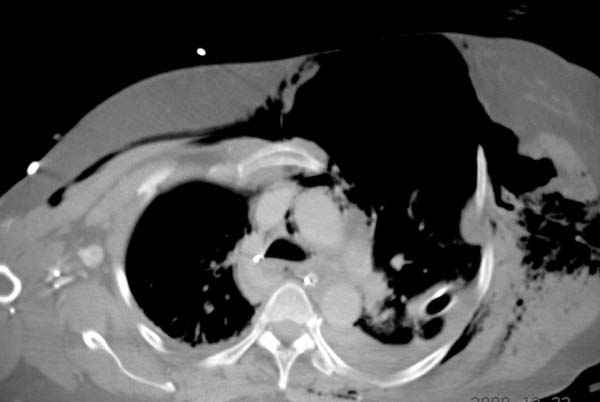

К нам поступила больная 56 лет после автоаварии в бессознательном состоянии, которая срочно заинтубирована в приемном отделении и сделаны необходимые исследования. Данные КТ и рентген показали перелом дистального бедра и Dissociation upper extremity - закрытый отрыв левой верхней конечности на уровне грудинно-ключичного сочленения и множественные переломы ребер.

На поверхности грудной клетки из-за полного разрыва грудной мышцы под кожей заметно биение сердца и след от ремня безопасности. Грудная клетка расширена из-за смещения верхней конечности вверх и латерально. Признаков васкулярного повреждения нет, и из-за отсутствия сознания не смогли определить наличия повреждения нервов.

Срочно в операционной наложен наружный фиксатор и травма хирургом поставлены трубки в плевральную полость.

В основном переломы ребер мы тоже не фиксируем, но учитывая, что в данной презентации, кроме разрыва грудинно-ключичного сочленения, дополнительно имелись множественные переломы ребер, некоторые сегментарные. После такой травмы трудно восстановить функцию западающей грудной клетки, и поэтому после дисскуссии с торакальным хирургом мы коллективно приняли решение зафиксировать переломы ребер тоже.

Исследование позвоночного столба входит в протокол исследования травматических больных и обычно делается при поступлении в первую очередь. КТ показала негативный результат.